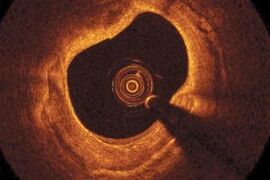

Imaging of blood flow reveals effects of drug use

Optical coherence Doppler tomography shows how cocaine damages cerebral blood vessels.

Bringing OCT to new markets

Joseph Schmitt of St Jude Medical believes entering new sectors is easier than ever, but planning is still the key.